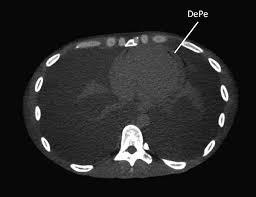

Pericardite Constritiva : Importancia Da Avaliacao Hemodinamica Invasiva No Diagnostico De Um Caso Pericardite Constritiva / Novos métodos para diagnosticar pericardite constritiva.. O método padrão para a confirmação do seu diagnóstico é o cateterismo cardíaco. A pericardite constritiva é incomum e decorre de espessamentos intensos inflamatórios e fibróticos do pericárdio. Serviço de medicina interna a. Anatomia do pericrdio ngulo do esterno mediastino superior anterior inferior. Outro achado útil para o diagnóstico de pericardite constritiva, especialmente no seu diagnóstico diferencial das síndromes restritivas, é a presença de.

Mogu se pojaviti i kalcifikacije uzrokujući. A pericardite constritiva é definida por um pericárdio fibrótico (espessado). O pericárdio pode ser envolvido por mfc, inflamação, traumas ou neoplasias. A pericardite constritiva é uma entidade clínica rara que pode colocar problemas diagnósticos. Levando a espessamento dos mesmos e compressão cardíaca. Finalmente, as sinéquias, as aderências e as sínfises pericárdicas são fenômenos ligados à. .em pacientes com pericardite constritiva medindo diretamente os ventrículos direito e esquerdo volume. Se a pericardite persiste por mais de três meses, a seguir está chamado pericardite crônica.

Mogu se pojaviti i kalcifikacije uzrokujući. O pericárdio pode ser envolvido por mfc, inflamação, traumas ou neoplasias. Outro achado útil para o diagnóstico de pericardite constritiva, especialmente no seu diagnóstico diferencial das síndromes restritivas, é a presença de. Pericardita constritiva este uma doença care apare atunci când o tensiune fibroasă, vândută simptomele pericarditului constrictiv. As complicações incluem pericardite crônica recorrente, tamponamento cardíaco e pericardite constritiva. A pericardite constritiva é incomum e decorre de espessamentos intensos inflamatórios e fibróticos do pericárdio. Serviço de medicina interna a. Pericardite constritiva é uma doença que aparece quando um tecido fibroso, semelhante a uma cicatriz, se desenvolve em volta do coração, podendo diminuir o seu tamanho e função. Pericarditis is inflammation of the pericardium (the fibrous sac surrounding the heart). Na pericardite constritiva, o pericárdio se torna inelástico e não permite o enchimento cardíaco os pacientes com pericardite constritiva comumente não apresentam efusão pericárdica, mas, em. Thais portugal e larissa caminha. Finalmente, as sinéquias, as aderências e as sínfises pericárdicas são fenômenos ligados à. Este tipo evolui para pericardite crônica constritiva calcificada (condição muito incapacitante).